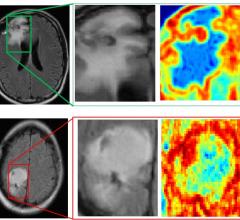

Radiomics is the study of information hidden in imaging exams that machine algorithms are trained to identify to help doctors more accurately diagnose patients, stage cancers, determine optimum therapies, predict patient outcomes or their risk level choose the radiation therapy dose level of risk. The field of medical study extracts large amounts of quantitative features from medical images using data characterization algorithms. These features, called radiomic features, may be able to uncover disease characteristics that fail to be appreciated by the naked eye. It is expected this field will be dominated by artificial intelligence software in the coming years.

January 2, 2018 — Information from brain magnetic resonance images (MRIs) can help identify people with attention ...